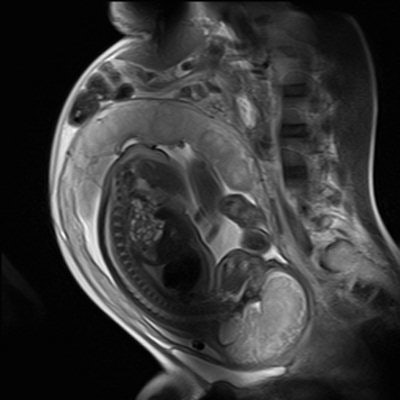

There is no firm evidence that clinical MR procedures during pregnancy produce adverse effects, the experts say. This sagittal half-Fourier acquisition single-shot turbo spin-echo (HASTE) image was used for planning further fetal images in other planes, and was taken at the Clinical Research Imaging Center, University of Edinburgh. Image courtesy of Janet De Wilde, PhD, and Dr. Scott Semple.The fetal trachea is filled with amniotic fluid and is hyperintense on T2-weighted images and hypointense on T1-weighted images. The lung parenchyma has intermediate signal intensity, which rises on T2-weighted images with increasing gestational age, and similarly decreases on T1-weighted images.

In cases of congenital diaphragmatic hernia, MRI can show herniation of the bowel loops and liver into the left hemithorax, with resultant hypoplasia of the left lung, Hayes noted. In another case of congenital cystic adenomatoid malformation, coronal MRI of a second-trimester fetus showed a large cystic malformation in the right hemithorax, with associated hydrops fetalis. Axial MRI of the thorax showed displacement of the heart, with a hypoplastic left lung.